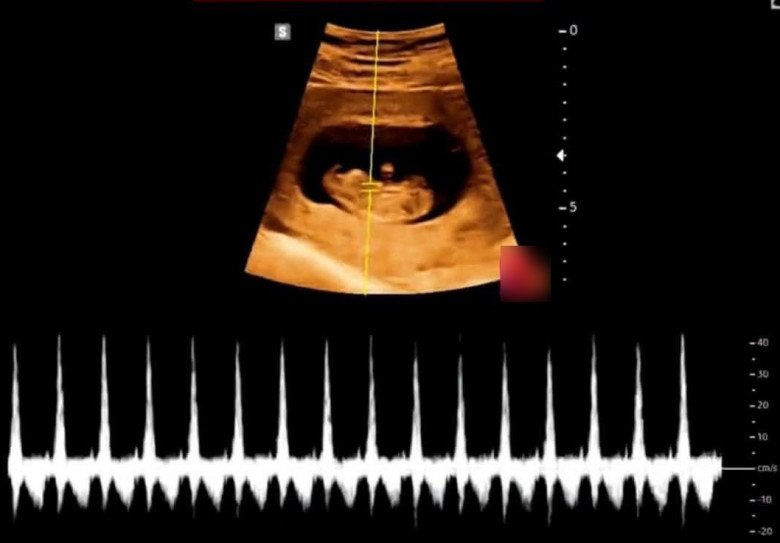

“Sau khi uống thuốc phá thai, thai phụ thấy máu ra nhiều nên cứ tưởng đã bỏ thai được rồi. Nhưng gần 1 tháng sau đó, chị thấy bụng to lên, vẫn có cảm giác như không hết nghén nên mới đến siêu âm. Khi đến gặp bác sĩ, chị bảo cảm giác như em bé vẫn còn. Đúng như linh cảm của mẹ bầu, khi siêu âm phát hiện thai được hơn 12 tuần tuổi.

Qua hình ảnh siêu âm thì thấy thai nhi không những không bị thuốc làm ảnh hưởng mà còn đang tiếp tục phát triển, tim thai cũng đập rất mạnh mẽ. Thai nhi còn nguyên vẹn thai, em bé có chân tay đầy đủ, cử động bình thường...”, bác sĩ Bun kể lại.